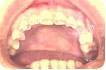

Hábito parafuncional de ranger os dentes e constitui um dos mais difíceis desafios para a odontologia restauradora, sendo que a dificuldade para sua resolução aumenta de acordo com a gravidade do desgaste dentário produzido. Fisiopatologicamente, o esmalte dentário é o primeiro a receber os prejuízos do bruxismo, e o desgaste anormal dos dentes é o sinal mais freqüente da anomalia funcional. O padrão de desgaste dental do bruxismo prolongado é, freqüentemente, não uniforme e mais severo nos dentes anteriores. O bruxismo noturno pode ocorrer em praticamente todos os estágios do sono, sendo observado predominantemente no estágio II e virtualmente ausente nos estágios III e IV, mais profundos. Quando relacionado ao sono, o bruxismo envolve movimentos rítmicos semelhantes ao da mastigação intercalados por longos períodos de contração dos músculos mandibulares. Essas contrações costumam ser fortes e até superar aquelas realizadas durante a mastigação normal consciente. Costumam durar o suficiente para produzir fadiga e dor muscular.

Hábitos funcionais do tipo bruxismo costumam levar ao desgaste dentário, má oclusão severa, trauma oclusal, fratura dentária e dores em determinados componentes do sistema mastigatório. O bruxismo é considerado uma das causas das desordens temporomandibulares devido à possibilidade de desencadear dor ou disfunção na musculatura mastigatória e /ou articulação temporomandibular.